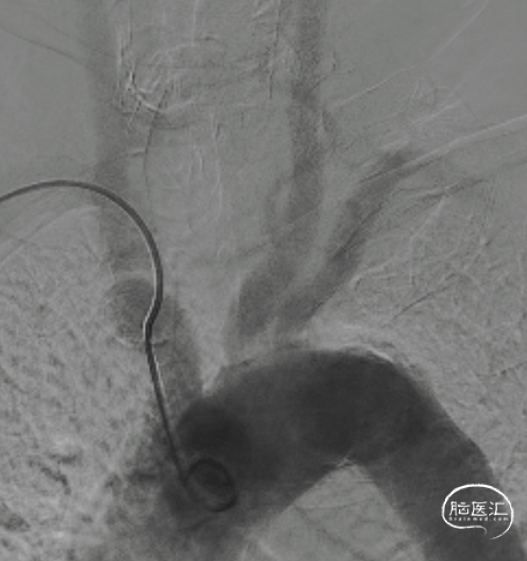

锁骨下动脉扭曲,III型弓。

本患者III型弓同时锁骨下动脉扭曲进行密网支架置入,对于经桡动脉和经股动脉建立通路要求均较高。因此选择赛诺神畅 6F-105 APEX TRA®经桡远端通路导引导管。

SIM2导管到位。

跨弓角度大,可见赛诺神畅 6F-105 APEX TRA®经桡远端通路导引导管柔软段跨越转弯处后沿泥鳅导丝一次顺利到达岩骨段。